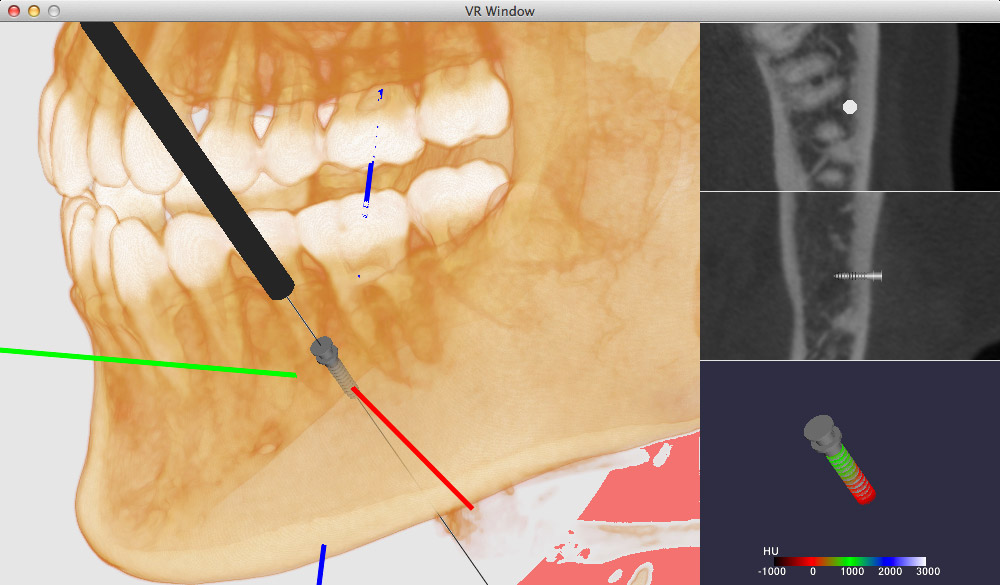

Cephalometric Evaluation of Facial Height Ratios and Growth。cephalometry-ceph-tooth-dental。矯正医選びのプロ視点①CT・セファロレントゲンによる精密な診断。「Radiographic Cephalometry」DVD付き書き込みはありません。A series of cephalometric radiographs depicting the patient。DVDは未開封です。成田崇矢の臨床『腰痛』 裁断済み 運動と医学の出版社。写真にて状態をご確認ください。健康・医学 Patient Blood Management Cardiac Surgery。中古品、自宅保管にご理解お願いいたします。医療・看護専門書19冊セット(バラ売り可)。#歯科#矯正#セファロ